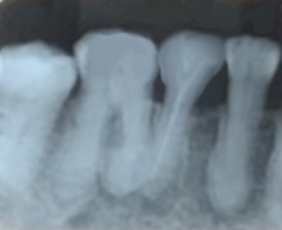

ปกติจะไม่มีอาการปวดหลังจากถอนฟันกราม เว้นแต่เป็นการถอนฟันที่มีปัญหาบางอย่าง เช่น รากฟันโค้งงอ รากฟันเป็นตุ้ม หรือมีรากฟันเกินขนาดเล็ก ทำให้การถอนฟันยากขึ้นและมีโอกาสรากฟันหัก หลังการถอนจึงอาจมีอาการปวดบ้างประมาณ 1-3 วัน การทานยาแก้ปวด แก้อักเสบ ที่ทันตแพทย์จ่ายให้ก็จะสามารถช่วยบรรเทาอาการได้

ภาพแสดงรากฟันเป็นตุ้มซึ่งเกิดในผู้สูงอายุที่มีแคลเซียมสะสมบริเวณปลายรากฟันซึ่งทำให้ถอนยากกว่าปกติเล็กน้อย